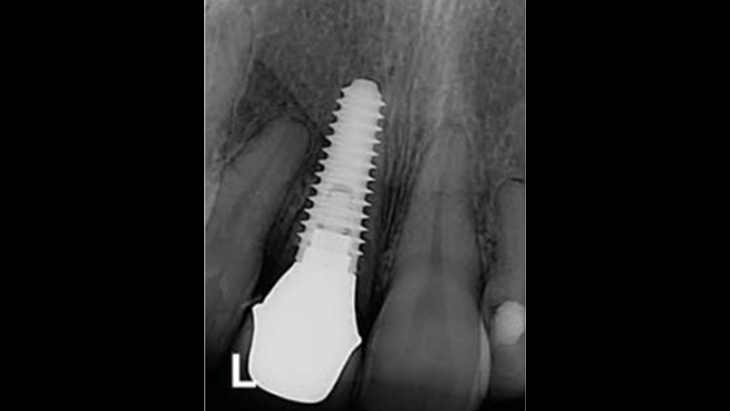

Clinical case: Replacement of fractured central incisor (#11) with immediate implant

& Root Membrane Technique

- Courtesy of Dr. Miltiadis Mitsias, Greece -

Keywords

AnyRidge, Root Membrane Technique, retrospective study, long-term study, immediate implants, bone resorption, bone preservation, Dr. Miltiadis Mitsias,survival, success, maxillary anterior, single replacement

Products:

AnyRidge implant system, Root Membrane kit

Reference

The Root Membrane Technique: A retrospective clinical study with up to 10 years of follow-up./Implant Dent. 2018 Oct;27(5):564-574

https://www.ncbi.nlm.nih.gov/pubmed/30161062